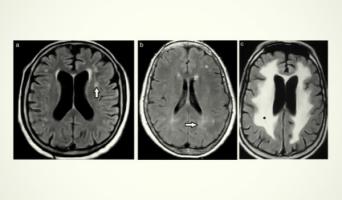

Sus principales líneas de investigación se han basado en trastornos del neurodesarrollo, psicosis de inicio temprano y prevención en Psiquiatría. Asimismo, ha participado en más de 76 proyectos de investigación competitivos públicos y privados, 58 de ellos como investigador principal. Es editor de 11 libros y 46 capítulos de libro, así como autor de más de 675 publicaciones científicas indexadas en revistas nacionales e internacionales.